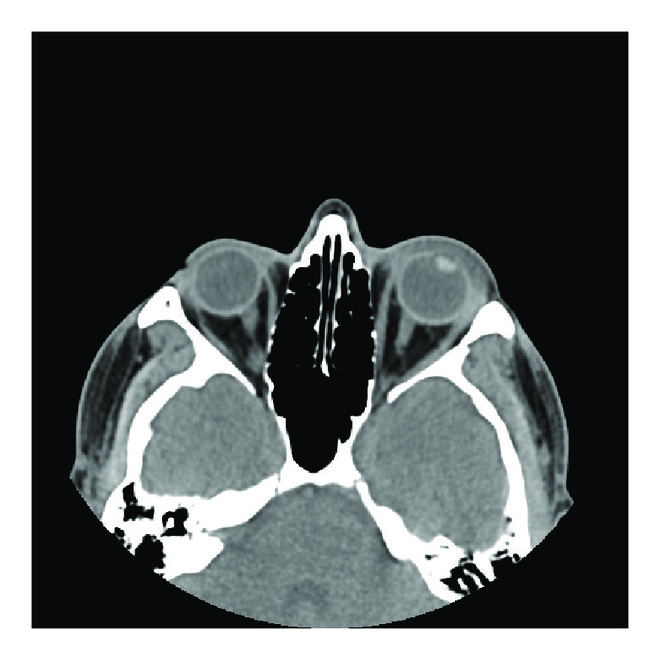

The patient was afebrile and had no leukocytosis. HIV testing was negative. Initial CT orbits displayed periorbital soft tissue swelling without evidence of orbital fractures or sinus disease (Figure 1(a)). He received a dose of intravenous ampicillin and sulbactam and was discharged home on a course of topical prednisolone, atropine, dorzolamide, and timolol all twice a day. The following day the patient has no light perception in the left eye with a keratitis developing along with increasing pain, proptosis, and now almost complete ophthalmoplegia.